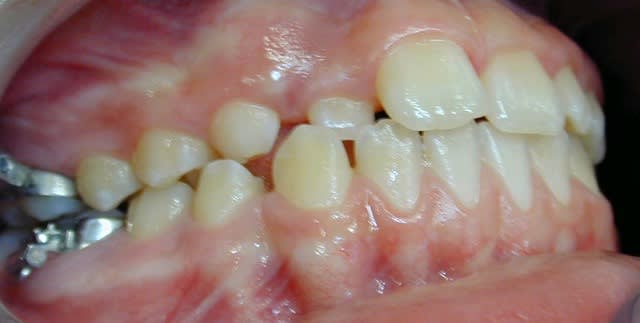

cas 2;Lea

BHG 9mois PUIS eln +2 LBs 15mois

l'occlusion;

NB: Dans les 2 cas , pas de version des inc infs!